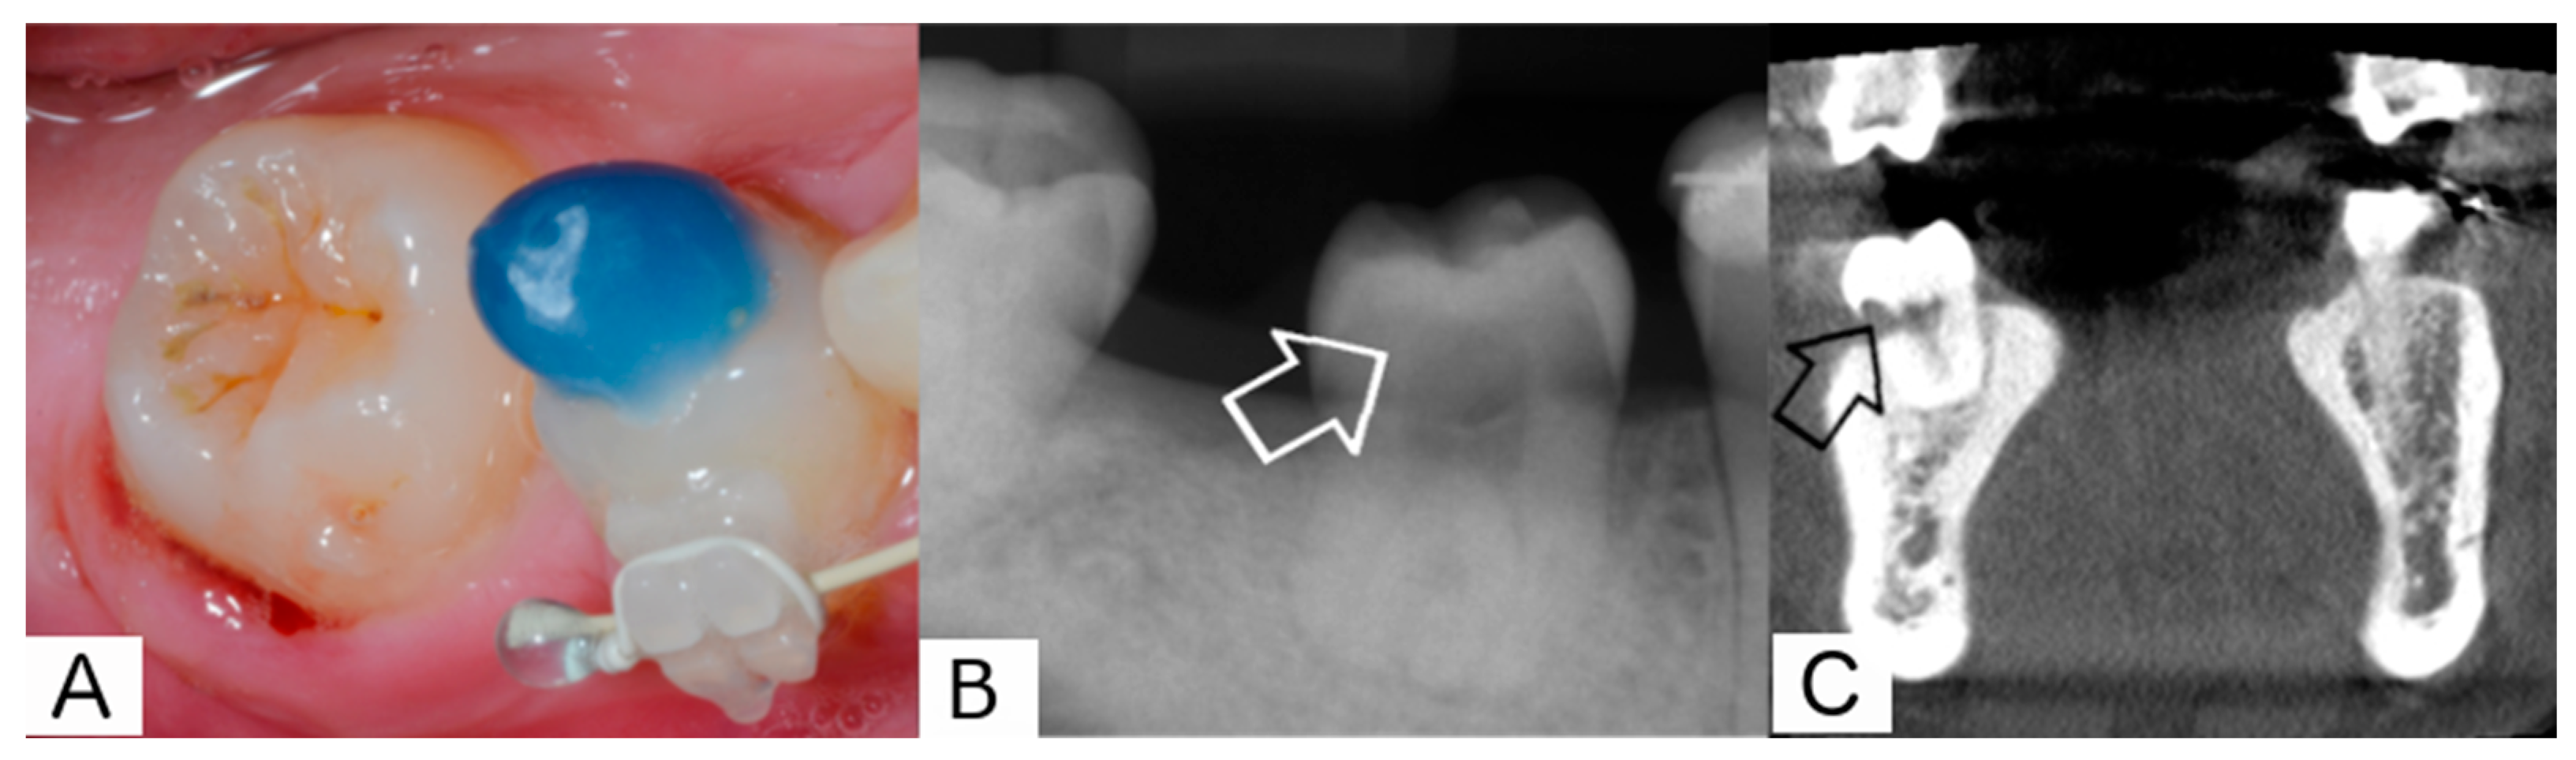

2. Report